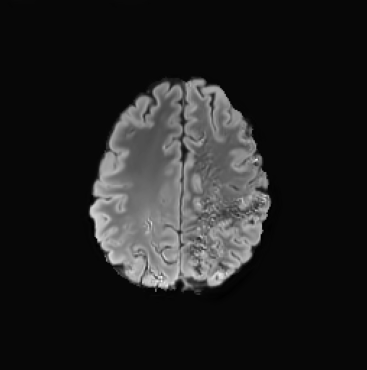

When computing with Eq. (9), the sum of the two components may not produce a perfectly coherent result. However, the incoherence is resolved by the next diffusion step, which fuses the two components better. This would not be the case if we simply computed with DDPM and then applied the mask only at the end of the sampling process. An illustration of this effect is presented in Figure 3, where we can observe how the normal image, generated by applying the mask solely at the conclusion of the sampling process (b), exhibits some artifacts and lacks a seamless transition between the edited and unedited regions.

4.3 Counterfactual Examples

In Figures 2 and 4 we display examples of healthy images and anomaly maps obtained with the different approaches. We can observe that f-Ano GAN is not able to generate credible counterfactuals and generally produces images of poor quality and unrealistic appearance. On the other hand, the approaches based on diffusion models are able to create more high-quality results. However, the ones obtained with CG and CFG seem to present some artifacts, which may not only impact the realism of the counterfactual examples but also the precision of the anomaly maps obtained from them. In order to better quantify the capability of these methods to accurately segment pathological areas, we compute the Dice scores of the anomaly maps they generate.